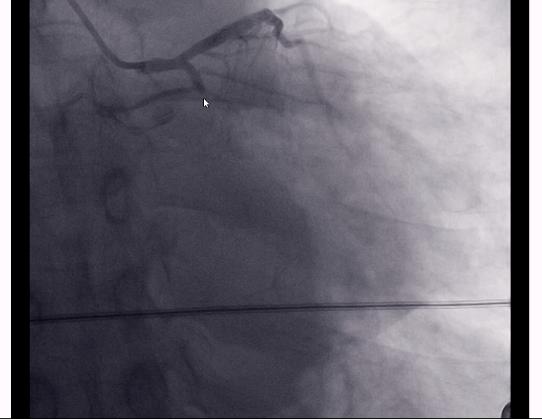

如图,可以看到这是左侧的冠脉造影。

畅通的是前降支,闭塞的是回旋支,已经完全闭掉了;